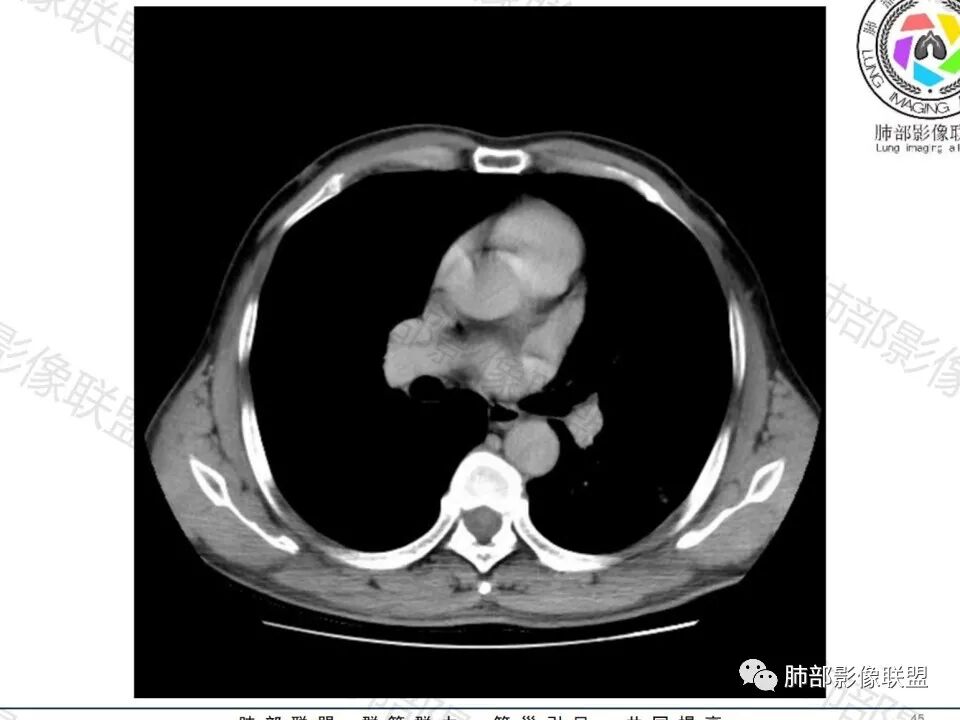

大家目前碰到多数结节是磨玻璃结节,对于实性结节的诊断反而陌生,其实性结节才是考验脑子的时候;

这枚结节的纵隔窗在没有调节窗位的情况下,已经很密实了,说明这个结节里面是软组织的成分,这与普通炎性结节(隐球菌等)的密度还是有区别的,很多年前就有人提出,纵隔窗显示越大,恶性可能越大;

结节周围有磨玻璃影,边界似清不清的,但是总体不如炎性晕征那么模糊;

增强的程度很难讲,但是不均匀强化是可以确定的;

有收缩力,但是很轻,按照常理,实性结节因为有占位效应,不太会有收缩力,但是叶间胸膜有凹陷。所以讲,这个结节还是开了放心。